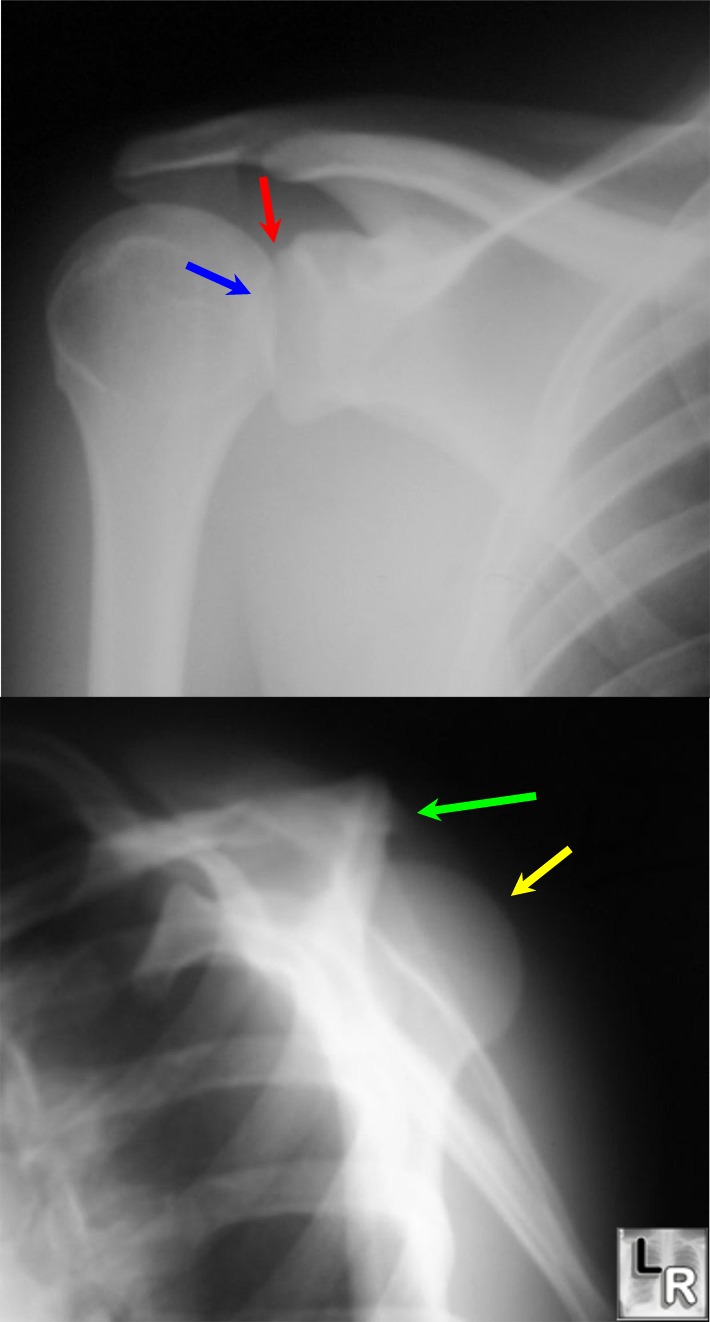

Light Bulb Sign Posterior Dislocation . Posterior shoulder instability and dislocations are less common than anterior shoulder instability and dislocations, but are much more commonly missed. Traditionally clinicians are taught to look for the ‘light bulb’ sign on anteroposterior (ap) radiograph as pathognomonic of a posterior. The light bulb sign refers to the abnormal appearance of the humeral head in posterior shoulder dislocation. The ‘light bulb sign’ suggests a posterior shoulder dislocation (figure 3). The smooth appearance of the internally rotated humeral head has been likened to a light bulb, so a posteriorly dislocated humeral head locked in internal rotation has been called the light bulb sign.

Posterior shoulder instability and dislocations are less common than anterior shoulder instability and dislocations, but are much more commonly missed. The light bulb sign refers to the abnormal appearance of the humeral head in posterior shoulder dislocation. The ‘light bulb sign’ suggests a posterior shoulder dislocation (figure 3). Traditionally clinicians are taught to look for the ‘light bulb’ sign on anteroposterior (ap) radiograph as pathognomonic of a posterior. The smooth appearance of the internally rotated humeral head has been likened to a light bulb, so a posteriorly dislocated humeral head locked in internal rotation has been called the light bulb sign.